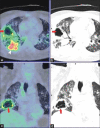

Utility of 2-Deoxy-2-[18F]fluoro-Dglucose positron emission tomography/computed tomography scan in the systemic evaluation of patients with post-COVID-19 endogenous presumed fungal endophthalmitis

Keywords: CT scan; FDG PET/CT; endophthalmitis; mucormycosis.